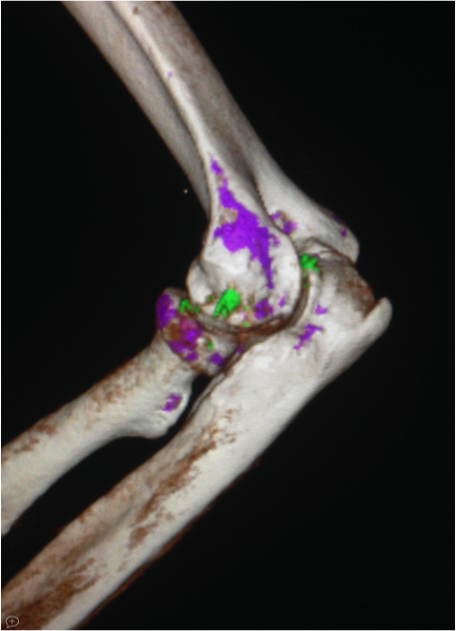

Jeff Carr, M.D., Professor and Cornelius Vanderbilt Chair, Radiology and Radiological Sciences, says the ability to scan with two energies at the same time allows for precise tissue characterization and the ability to remove bones and metal artifacts that can obscure imaging of critical structures.

The scanner is also able to freeze motion, which allows imaging of small structures at a higher resolution. Moving structures that would previously be unrecognizable on an older CT scanner are also produced with better clarity.

Elbow Arthritis Imaging – The new CT scanners provide not only high resolution imaging of the bones (3D) but also identify the chemistry, in this case the specific crystals seen in gouty arthritis are colored green.